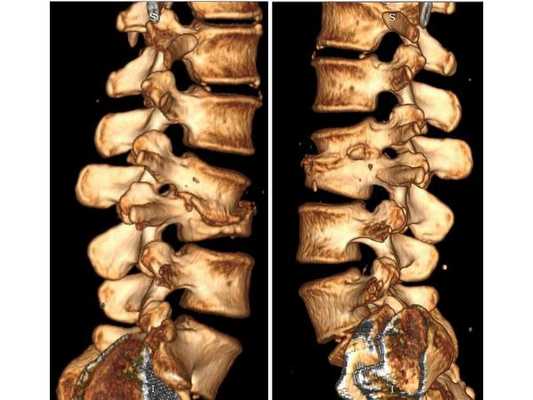

КТ пояснично-крестцового отдела позвоночника показала состояние после перенесённого спондилодисцита L2-L3 (воспалительного заболевания инфекционного характера) с разрушением тела L3 позвонка и кифотической деформацией (искривлением позвоночника) на данном уровне.

Состояние после перенесённого спондилодисцита L2, L3 позвонков с формированием абсолютного стеноза (критического сужения просвета в позвоночном столбе) на уровне L2-L3 и развитием нижнего парапареза

Пациентке проведена операция: транспедикулярная фиксация позвоночника L1-L4 и ламинэктомия L2 (удаление дужки позвонка с целью декомпрессии). Ход операции: • При положении пациентки лёжа на животе в проекции остистых отростков L1-L4 произведён прямой вертикальный разрез мягких тканей размером 10 см. • Надкостницы поперечных отростков и дугоотросчатых суставов отделены от костей. Кровотечение остановлено при помощи электрокоагуляции по ходу доступа. • Под контролем рентгена выявлены ножки L1 и L4 позвонков и сформированы каналы в тела самих позвонков, через которые в их ножки введены моноаксиальные педикулярные винты. • Проведена ламинэктомия позвонка L2. При ревизии твёрдой мозговой оболочки, окружающей спинно-мозговые корешки, на уровне L2-L3 позвонков обнаружены выраженные изменения рубцово-спаечного характера. • Рана промыта при помощи физраствора и раствора перекиси водорода. Поверх твёрдой мозговой оболочки уложена гемостатическая губка. Установлены две продольные штанги, закручены стопорные гайки. • В конце на рану наложен послойный шов нитью Викрил и асептическая повязка.

После операции в неврологическом статусе наблюдается положительная динамика: умеренный парапарез в нижних конечностях почти полностью регрессировал, жалобы на "онемения в ногах" также исчезли. На контрольной КТ видно состояние после успешной декомпрессии на уровне L2-L3 и установки транспедикулярной фиксирующей системы на уровне L1-L4.

Учитывая анамнез и результаты КТ пояснично-крестцового отдела позвоночника, можно предположить, что во время стационарного лечения у пациентки на уровне L2-L3 позвонков развился спондилодисцит. Характерным признаком этого заболевания в острой фазе является уменьшение рентгеновской плотности тел позвонков. Но во время проведения компьютерной томографии плотность тел L2 и L3 позвонков была высокой, что свидетельствовало о завершении воспалительного процесса и склерозировании тел позвонков. Вероятнее всего, антибактериальное лечение погасило воспаление не только в брюшной полости и почках, но и в позвоночнике. Однако после выписки из больницы, при переходе из лежачего положения в вертикальное, у пациентки стала увеличиваться кифотическая деформация. Патология привела к образованию стеноза позвоночного канала на уровне L2-L3, что и спровоцировало возникновение нижнего парапареза. С помощью транспедикулярной фиксации L1-L4 и декомпрессии на уровне L2 удалось устранить неврологические симптомы и стабилизировать позвоночный сегмент, то есть "экстренная" помощь была оказана успешно.